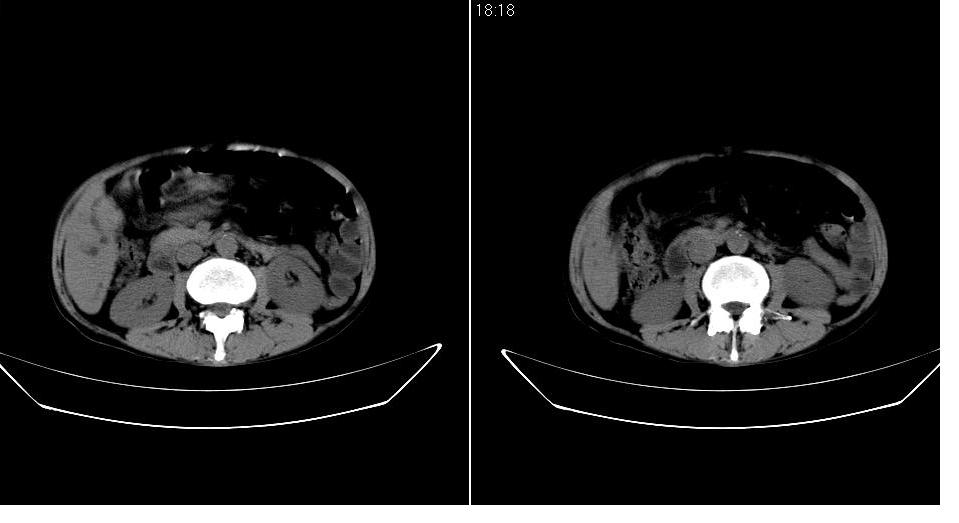

男 55岁,黄染二十余天,无明显腹疼及发热,病人拒绝增强,因没钱.

考虑壶腹周围ca办阻塞性胆道系统扩张、肝转移。 强烈要求增强!

考虑胰头ca伴阻塞性胆道系统扩张、肝转移。建议增强!

考虑胰头癌伴肝门部淋巴结转移及胆管扩张或是肝门部胆管癌伴胰头周围淋巴结转移.

考虑胰头癌伴肝门部淋巴结转移、肝脏转移及胆管扩张。

胰头增大,密度稍低,胰腺体尾部缩小,肝内胆管明显扩张,肝右叶低密度影。 考虑胰头癌并阻塞性肝内胆管扩张,肝内转移灶?建议进一步增强扫描。